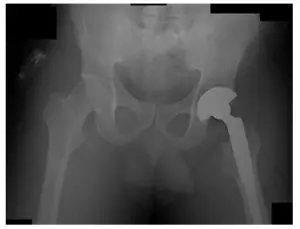

Left THA Revision performed in 2011.

X-Ray of Pelvis during operation